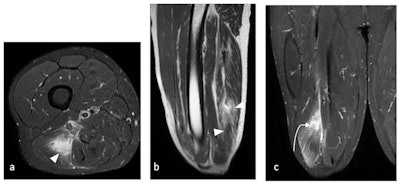

Muscle injuries are frequent in football players, mostly in hamstrings, quadriceps, adductors, and calf muscles. Ultrasound is a helpful primary imaging modality, but MRI remains the mainstay in the diagnosis of muscle injuries, identifying precise anatomical location and pattern of injury that might range from interstitial edema without fibers distortion to more severe injury pattern with fibers and architecture distortion, laceration, and gap. The injury might involve one or more of these components: muscle fibers, myoaponeurosis/fascia, myotendinous junction, and tendon.

"Intramuscular degloving of the rectus femoris is a pattern of injury associated with kicking where dissociation of the inner (indirect head) and outer (direct head) muscle layers result in bull's eye appearance on MRI," they added.